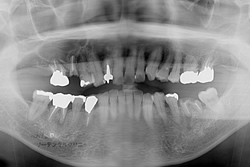

必要な場合先ず最初に患者様のお口の状態をよく知るためにレントゲン撮影をさせていただきます。

虫歯の状態や、歯周病の進行状態を知るための歯槽骨の状態、親知らずや顎関節の状態 などを確認致します。